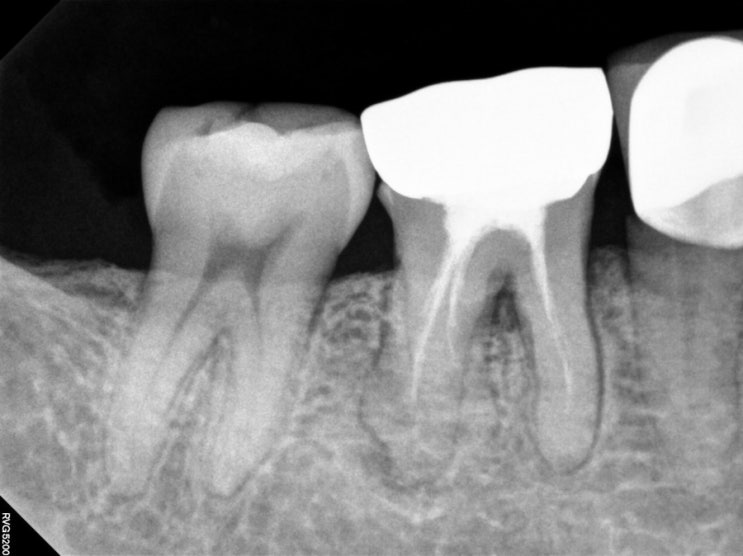

원주임플란트 - 과연, 진단이 정확할까? 원주치과 x 예쁜약국 오지랖 에피소드 / 단계동 야간진료치과 (화 , 목 9시 ) feat. 빅터프랭클 영혼을 치유하는 의사

조제중이었다. 120포. 약을 똑똑 약주걱에 떨어뜨리고 있는데 종소리와 함께 약국 문이 열렸다. 베이지색 ...